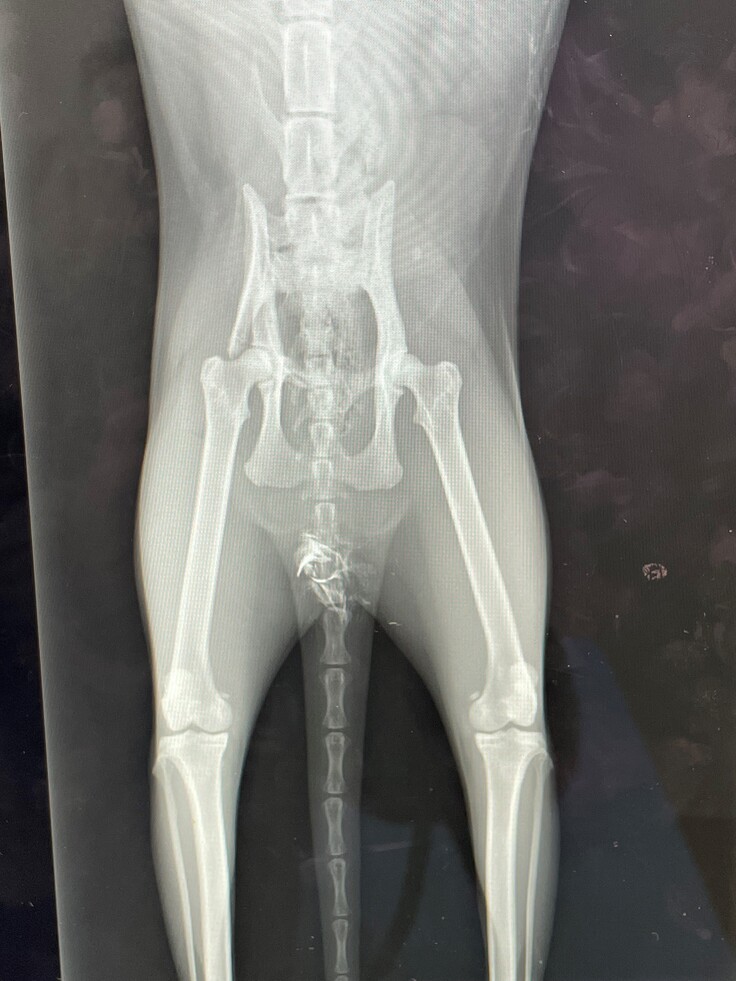

骨盤個骨折、肺座礁に加え肝機能障害が見つかりました。

骨盤骨折手術費用、肺座礁・肝機能障害の入院治療費を集めたいです。

シャケちゃんの骨盤骨折治療費と肝機能障害・尿管破損の治療費と経過観察・検査・投薬費用ににあてます。

令和6年12月30日〜令和7年2月7日の間で応急処置、骨盤骨折・尿管破損の必要な手術は完了しました。

(4)診断書

A動物病院

B動物病院